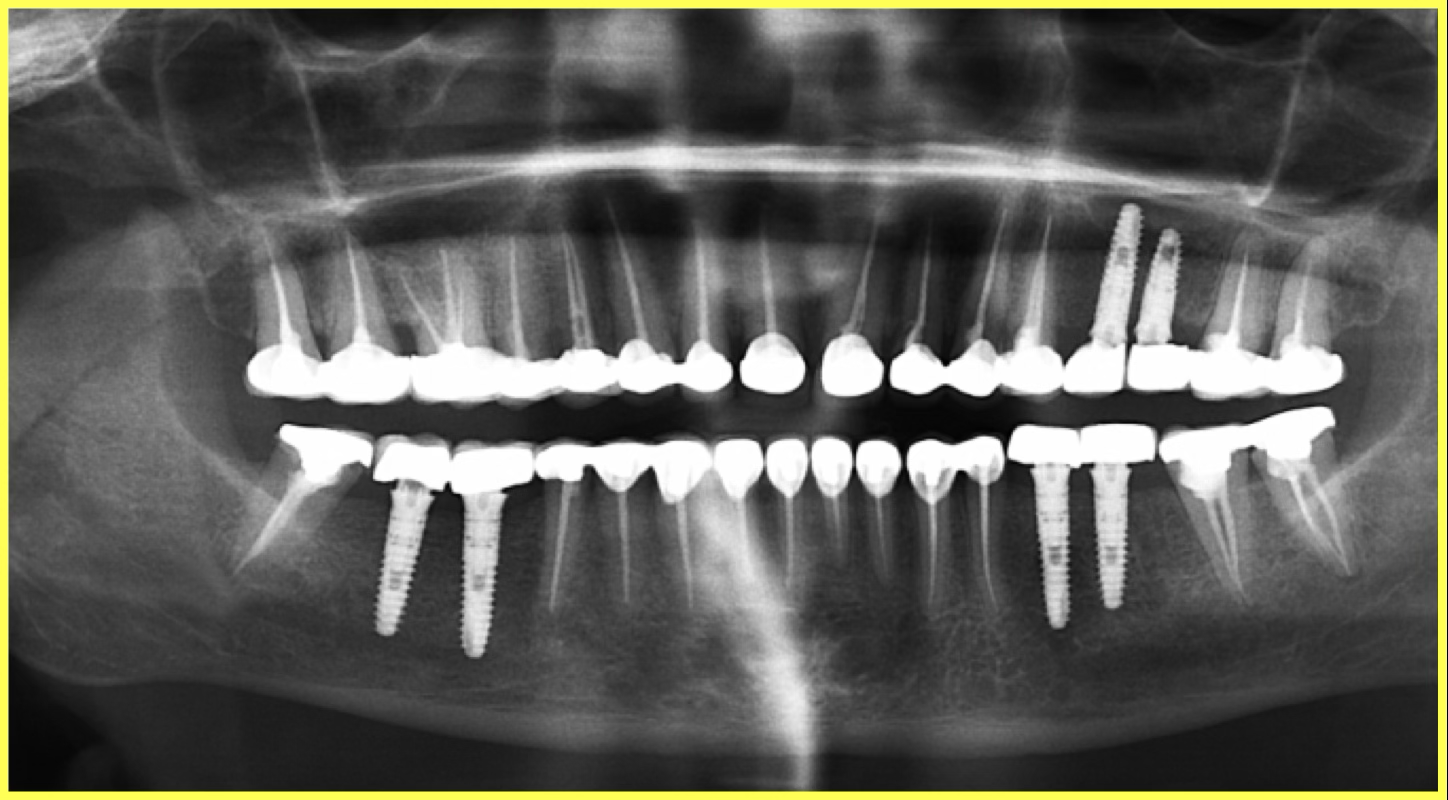

Final result

Permanent Porcelain Fused to Metal (PFM) crowns were custom-fabricated and cemented. Implants were delayed loaded after 3 months of healing.